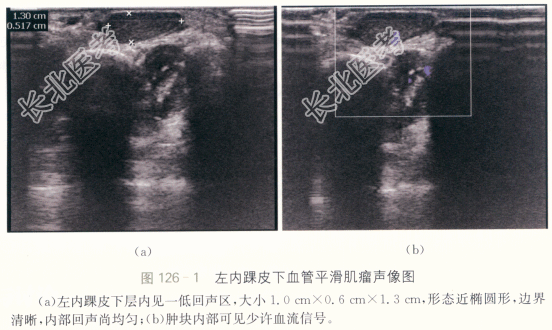

患者,女性,52岁,因“发现左内踝肿块2年余”就诊。患者两年前发现左内踝肿块,肿块无明显增大。患者既往无外伤史,无手术史,无其他器官肿瘤史。

患者左内踝皮下触及肿块,大小约1cm×1cm。质软,无压痛,活动度好。周围皮肤颜色正常,无皮肤破溃,无手术瘢痕。

血管平滑肌瘤。